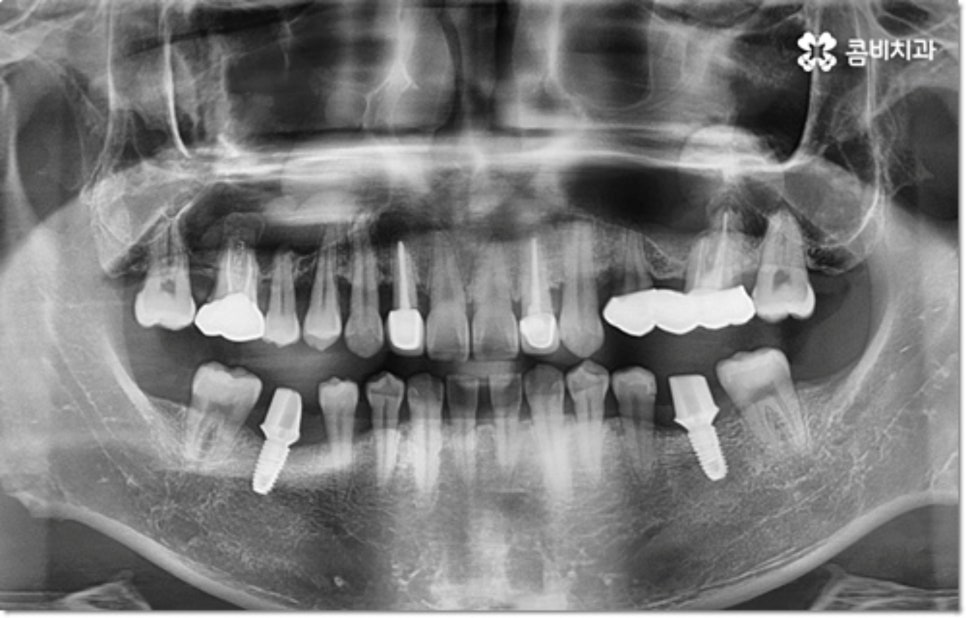

사진에서 볼 수 있는 사례는 아랫니가 크게 부러져서 빠졌을 때 아랫니임플란트 시술을 통해 수복을 해 준 거예요. 이때 빠른 일상 복귀를 원하는 만큼 기간이 얼마나 오래 걸리는가 하는 것은 임플란트 시술을 받으시는 분들의 가장 주된 관심사 중 하나라고 할 수 있는데요.

임플란트 시술 기간은 환자분들의 상황에 따라 달라지는 것이지만 보통 빠르면 36개월, 뼈이식이나 상악동 거상술과 같은 선처치가 필요한 경우 또는 회복 기간이 생각보다 오래 걸리는 경우에는 8개월1년 넘게 까지도 걸릴 수 있습니다. 혹시 모를 부작용으로 재시술을 받게 되는 경우도 있기 때문에 치과를 선택하실 때 말씀드린 의료진의 숙련도 외에도 여러 가지 사항들을 꼼꼼하게 따져보실 필요가 있어요. 3D CT 와 같은 정밀 장비로 환자분들의 잇몸 상황 또는 교합 등을 세밀하게 살펴보고 그에 맞춰 무리하지 않게 임플란트 식립을 진행하는 치과에서 검진부터 사후관리까지 체계적으로 케어받는 것이 중요한 거예요.